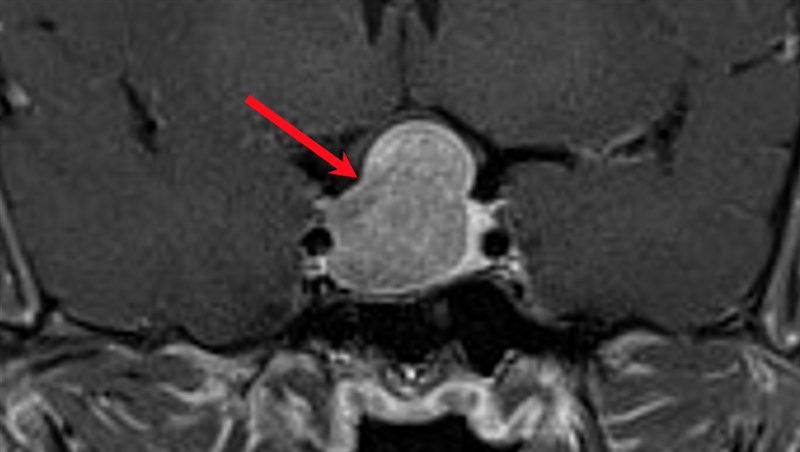

術前腦部核磁共振影像之正面切面,紅色箭頭處為腦下垂體腫瘤之位置。圖/馬偕醫院提供

馬偕醫院神經外科主治醫師詹雲凱表示,陳先生經由內分泌暨新陳代謝科診斷為肢端肥大症後,核磁共振影像進一步定位長在腦下垂體的腫瘤;以往類似陳先生這樣必須接受腦部手術的病人,必須先在頭部劃下一道長長的手術傷口,並取下大範圍的頭骨後,才能進行腦部腫瘤的手術切除。